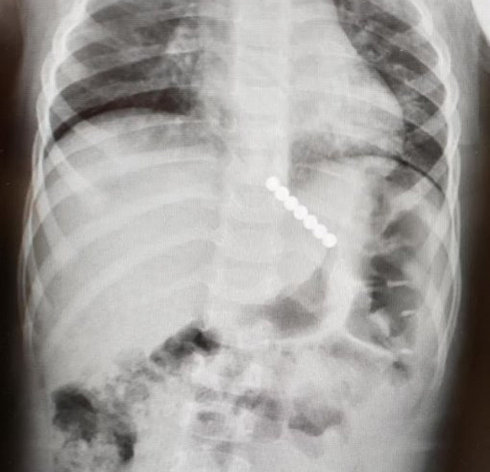

Израильские врачи спасли 2-летнюю девочку, проглотившую 7 магнитов

В течение часа с момента поступления в приемное отделение медики успешно извлекли инородное тело из желудка маленькой пациентки.

После первичного осмотра малышки были немедленно вызваны специалисты по эндоскопии и врач-анестезиолог. Было решено оперативно извлечь магниты, пока они находятся в желудке.

"Каждая минута в такой ситуации имеет критическое значение. Магниты перемещаются и могут притягиваться друг к другу через стенки кишечника. Это может привести к тяжелому повреждению органов и внутреннему кровотечению", - пояснила д-р Ишах-Адив.